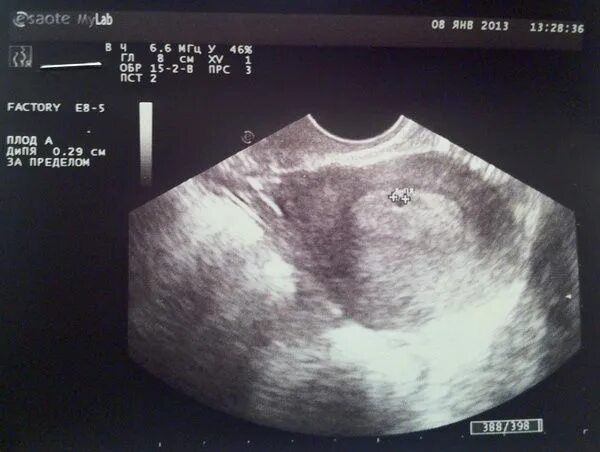

Беременность три недели и три дня